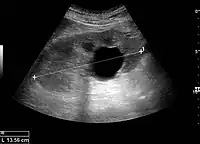

Renal ultrasonography of a simple renal cyst with posterior enhancement.